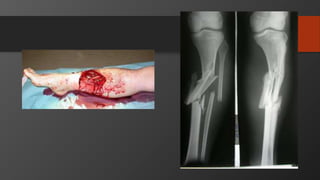

Tibia Shaft Fractures

• Mechanism

• Low energy usually torsional injury

• High energy, e.g. road-traffic accident

• Presentation

• Swelling

• Pain

• Inability to bear weight

• Always rule out open fractures

• Always check for compartment syndrome

• Always check neurovascular status

Tibial Plateau Fracture

• Imaging:

• X-Ray: AP, Lateral

• Full length

• Knee and ankle also